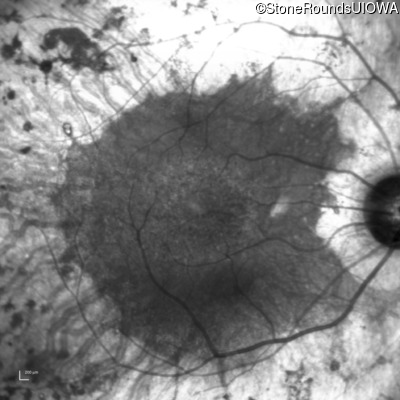

Infrared Fundus Photograph - Right - 20/63 -1

Exemplar